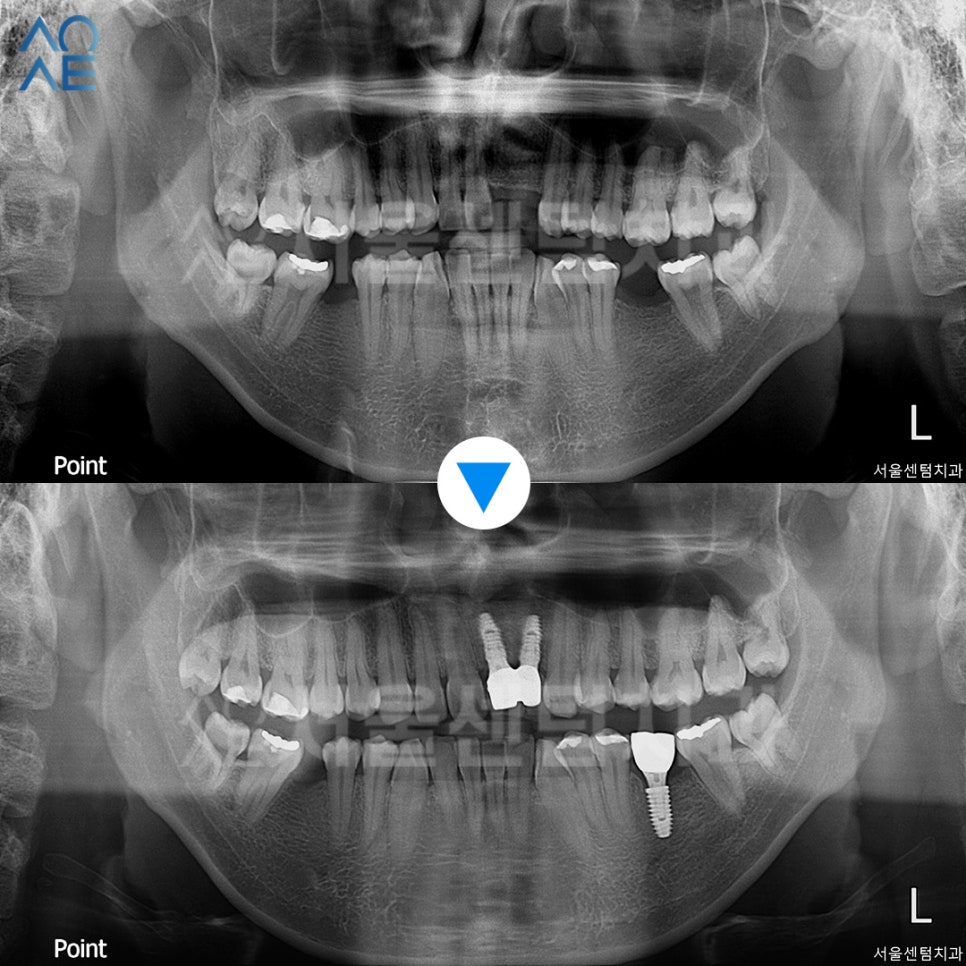

| (1) 현 상태🔹 상실한 치아는 총 4개 (앞니는 2개)🔹 전체적으로 잇몸이 조금 내려가있음🔹 충치치료도 필요해보임 |

| (2) 임플란트 수술 계획🔹왼쪽 아래 어금니부터 진행🔹4주 후 왼쪽 앞니쪽도 수술 진행 |

왼쪽 아래 어금니 임플란트 수술 후 모습입니다.

아직 1차만 진행한 상태이며

잇몸뼈가 부족하여 뼈이식도 함께 진행했습니다.

첫 치료로부터 3주 후 앞니 수술도 했습니다.

앞니도 뼈이식을 함께 진행하였고

앞니 임플란트 포함하여 총 3개 수술을 마쳤습니다.

2차수술까지 진행하여

시간이 조금 걸렸지만

결과가 좋은 편이라 다행입니다.